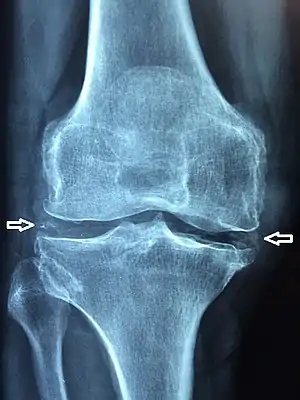

X-ray, CT, or other imaging usually shows accumulation of calcium within the joint cartilage, known as chondrocalcinosis. There can also be findings of osteoarthritis.[4][3] The white blood cell count is often raised.[3]

Medical imaging, consisting of x-ray, CT, MRI, or ultrasound may detect chondrocalcinosis within the affected joint, indicating a substantial amount of calcium crystal deposition within the cartilage or ligaments.[2] Ultrasound is a reliable method to diagnose CPPD.[7] Using ultrasound, chondrocalcinosis may be depicted as echogenic foci with no acoustic shadow within the hyaline cartilage[8] or fibrocartilage.[7] By x-ray, CPPD can appear similar to other diseases such as ankylosing spondylitis and gout.[2][3]

Calcium pyrophosphate dihydrate crystals are associated with a range of clinical syndromes, which have been given various names, based upon which clinical symptoms or radiographic findings are most prominent.[12] A task force of the European League Against Rheumatism (EULAR) made recommendations on preferred terminology.[5] Accordingly, calcium pyrophosphate deposition (CPPD) is an umbrella term for the various clinical subsets, whose naming reflects an emphasis on particular features. For example, pseudogout refers to the acute symptoms of joint inflammation or synovitis: red, tender, and swollen joints that may resemble gouty arthritis (a similar condition in which monosodium urate crystals are deposited within the joints). Chondrocalcinosis,[2][3] on the other hand, refers to the radiographic evidence of calcification in hyaline and/or fibrocartilage. "Osteoarthritis (OA) with CPPD" reflects a situation where osteoarthritis features are the most apparent. Pyrophosphate arthropathy refers to several of these situations.[15]